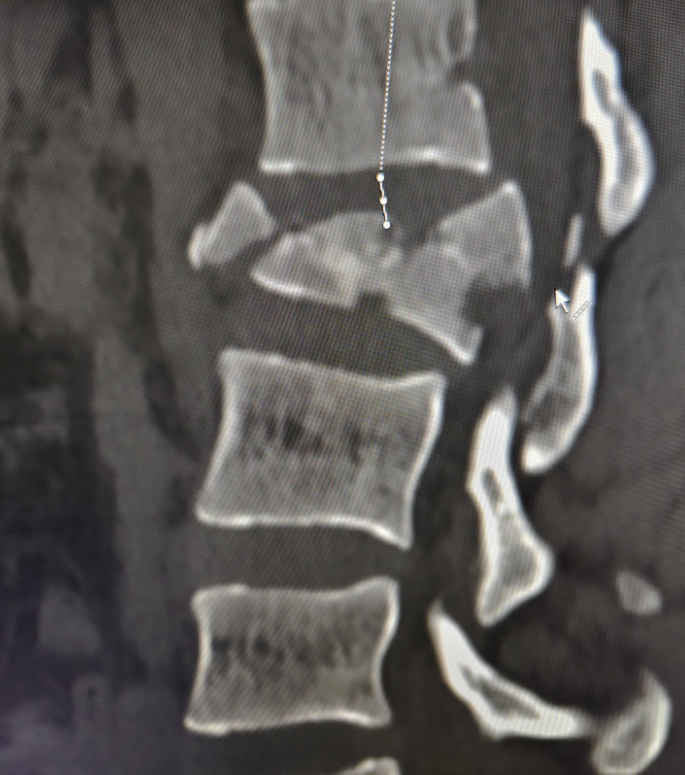

31歲的患者邊某因外傷致腰2椎體爆裂骨折前來(lái)就診,詹志強(qiáng)醫(yī)生帶領(lǐng)洛隆縣人民醫(yī)院醫(yī)生索東華爾丹、多吉次仁為患者行全麻下“后路腰2椎體骨折經(jīng)椎弓根釘棒復(fù)位內(nèi)固定術(shù)”。

手術(shù)耗時(shí)90分鐘,順利完成,術(shù)中5個(gè)釘?shù)狼锌陂L(zhǎng)度僅為2cm、出血僅約60ml,術(shù)中術(shù)后攝片見(jiàn)椎管內(nèi)占位的骨碎片已完全復(fù)位,椎體高度相比術(shù)前也得到明顯恢復(fù)。